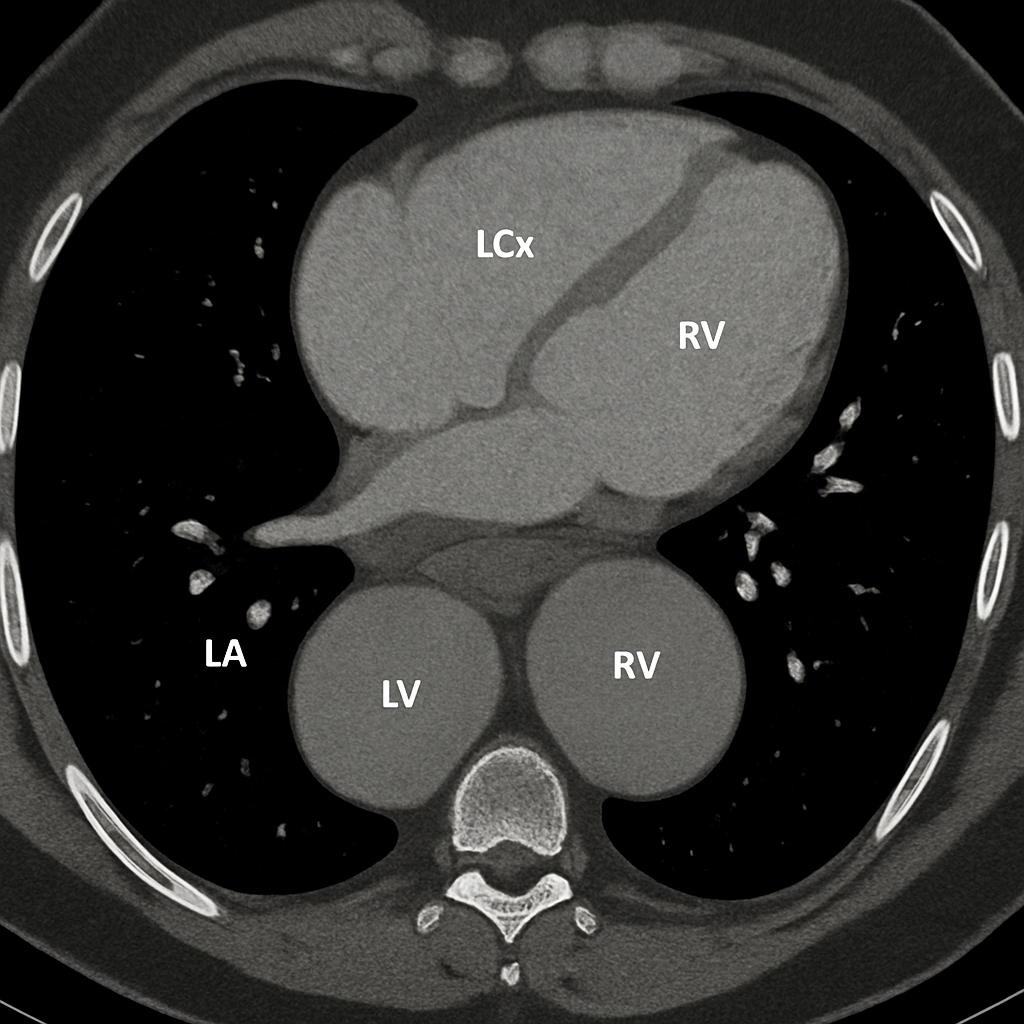

AI-generated comprehensive cardiac phantom with all four chambers, valves, coronary arteries, great vessels,...